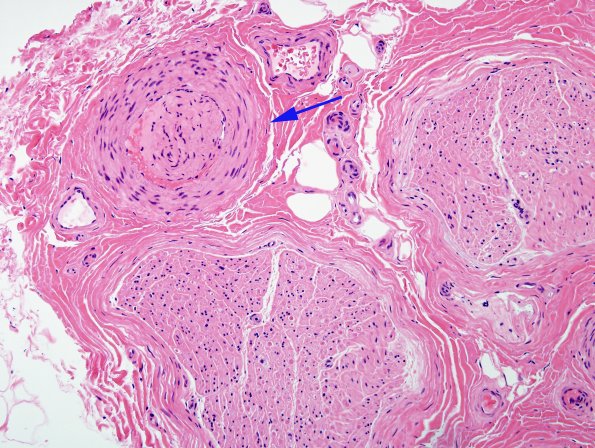

The vessels telescope internally (arrow) near crushed ends of nerve. (H&E)